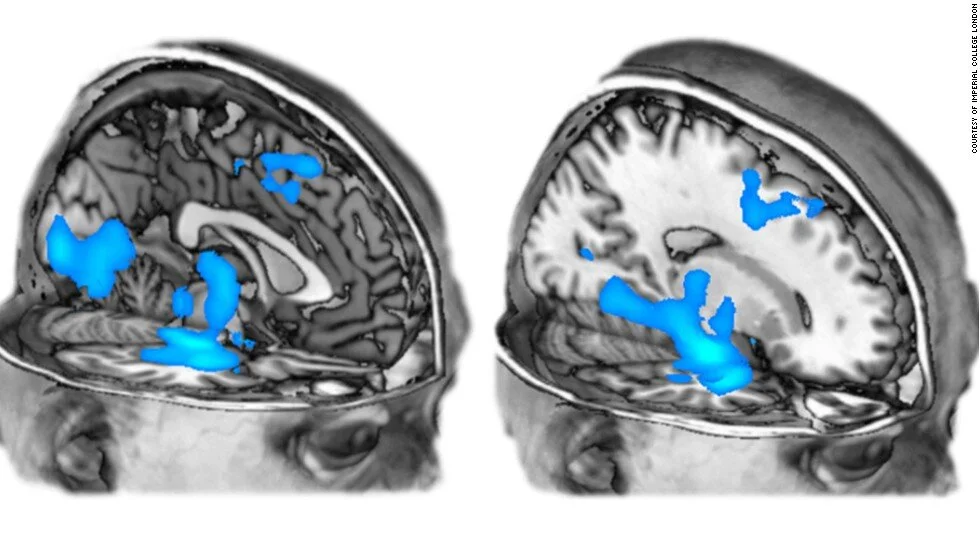

Although recent neuroimaging research indicates strong parallels between very advanced meditators and individuals on a psychedelic trips (such as the decrease in the amount of activity in structures of the brain associated with self-reflective thought - the ‘default mode network’), there is as yet little indication that repeated psychedelic trips build the kind of structural changes in brain functioning seen in long-term meditators.